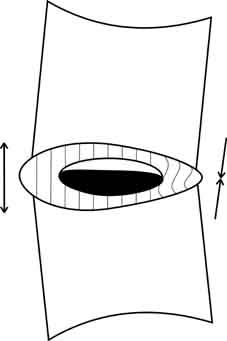

Тело вышележащего позвонка обретает дополнительную степень свободы, и может смещаться в горизонтальной плоскости чаще кзади, что обусловлено строением дугоотросчатых суставов (так называемый «дегенеративный сдвиг»). Кроме того, увеличивается и вертикальная подвижность краёв соседних позвонков, что при форсированных сгибании и разгибании приводит к возникновению отрицательного давления в «полости» межпозвонкового диска и как следствие этого к появлению «вакуум-феномена».

При наличии грыжи межпозвонкового диска газ может определяться в полости её при компьютерной томографии.

Больной мужчина 48 лет поступил в отделение нейрохирургии с болями в поясничном отделе позвоночника, корешковыми жалобами. Оперирован 4 года назад по поводу грыжи диска L4-5 (гемиламинэктомия L4). На обзорных снимках поясничного отдела позвоночника выявлены признаки остеохондроза, смещение тел L3, L4 кзади на 3 и 4 мм соответственно. Для исключения гипермобильности были произведены функциональные рентгенограммы в положении максимального сгибания и разгибания, на которых значительного увеличения листеза выявлено не было, отмечалось увеличение вертикальной подвижности тел позвонков (в основном в сегментах L3-4и L4-5).

Кроме того, в проекции дисков L3-4, L4-5 и L5-S1 визуализировались треугольной формы просветления газовой плотности, которые и были расценены как «вакуум-феномен» (на данной рентгенограмме газ чётко виден только в диске L3-4)